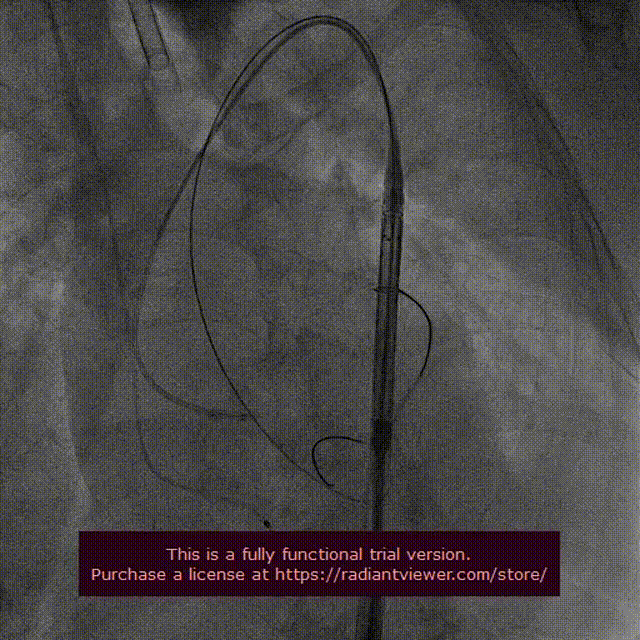

VenusA-Plus®输送器在snare辅助下顺利过弓跨瓣,将VenusA-Plus®L26瓣膜精准定位到无冠窦最低点。

起搏120次/分,VenusA-Plus®L26标准位快速释放,释放至三分之二处,造影发现瓣膜位置不佳,下滑严重,快速进行回收,重新定位释放。患者术前EF值只有42%,考虑到患者心功能不全引起的风险,将瓣膜快速释放,造影发现第二次释放位置良好。